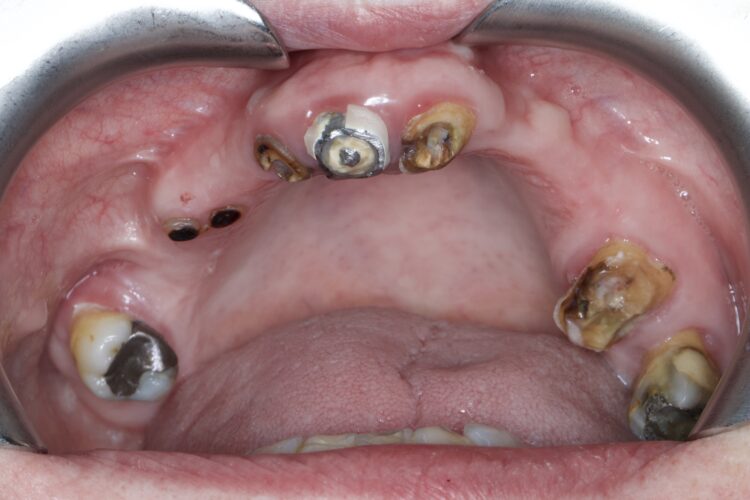

1. Carious roots:

We have all seen those patients that have dark brown/black carious roots down to gum level. Incredibly these roots rarely cause any real symptoms and may persist for years without any problem. You could easily argue that they should be removed, however they are often serving us by preventing bone and soft tissue loss. I will usually only remove these just when I’m ready to place an implant.